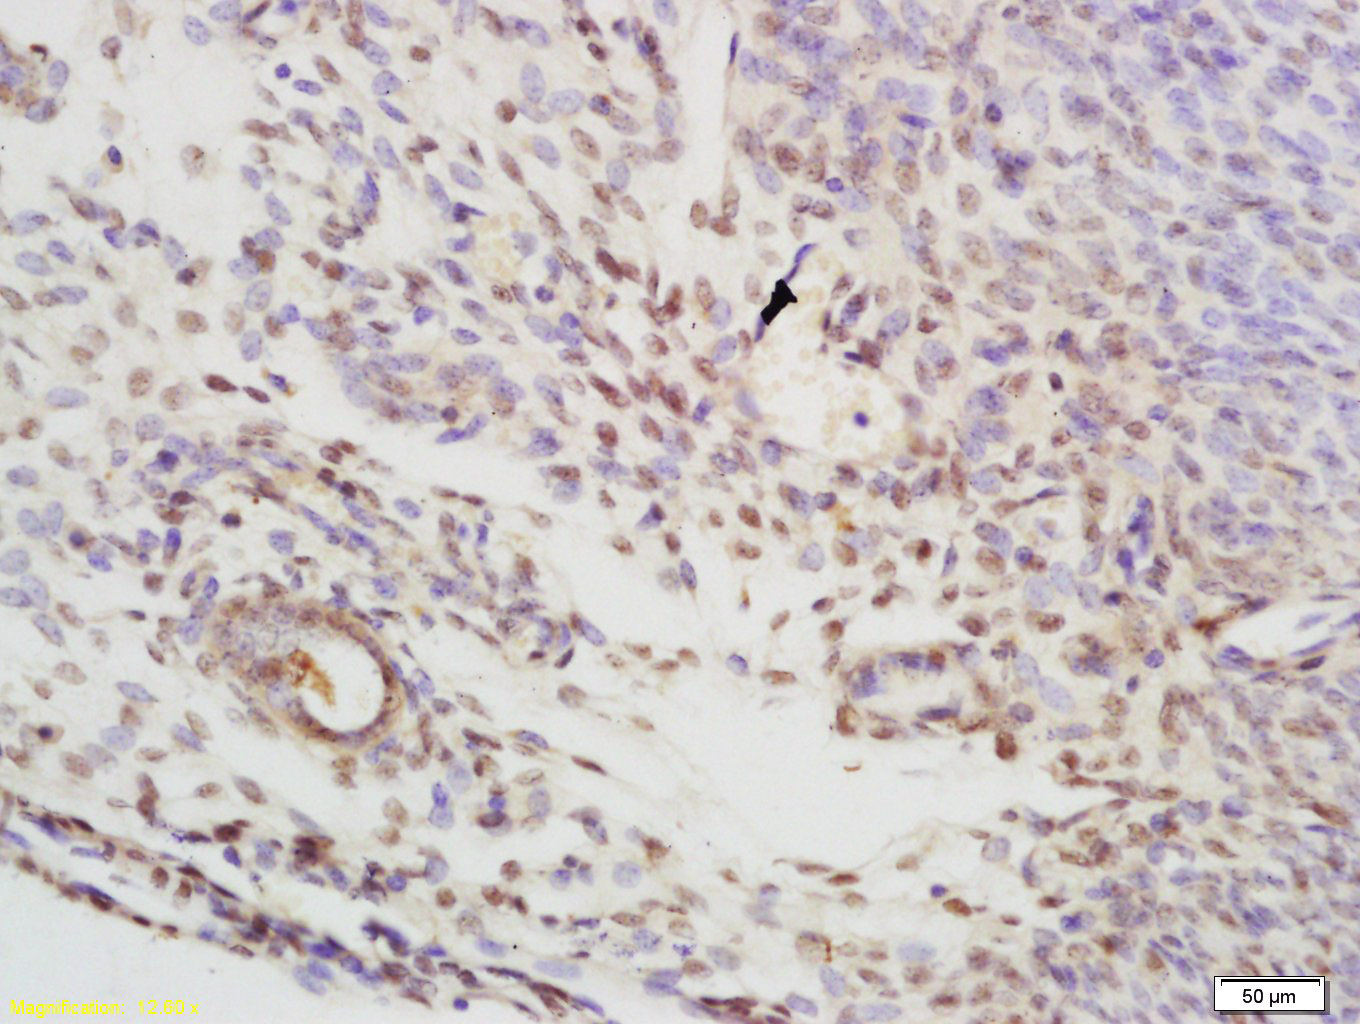

Antigen retrieval: citrate buffer ( 0.01M, pH 6.0 ), Boiling bathing for 15min; Block endogenous peroxidase by 3% Hydrogen peroxide for 30min; Blocking buffer (normal goat serum,C-0005) at 37℃ for 20 min;

Incubation: Anti-CBX1 Polyclonal Antibody, Unconjugated(bs-8169R) 1:200, overnight at 4°C, followed by conjugation to the secondary antibody(SP-0023) and DAB(C-0010) staining